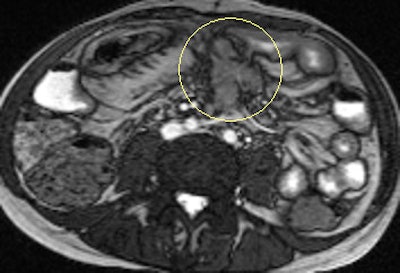

Diffusion-weighted imaging (DWI) has recently been added to the London hospital's MRE protocol. Three b values (b = 0, 100, and 800) are used, with axial images through the upper and lower abdomen obtained. The purpose of this is to help identify actively inflamed loops of bowel by the presence of restricted diffusion within the affected bowel wall, she elaborated.

"From our experience, MRE can be used to show a significant reduction in inflammatory activity (as demonstrated by reduced mural thickening, edema, and enhancement) following treatment with such agents. DWI may have a role in response assessment with a predicted decrease in the degree of restricted diffusion. However, as yet there are no published papers on this subject," explained Griffin.